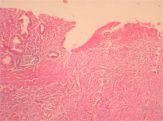

Details various forms of acute and chronic gastritis, intestinal metaplasia, peptic ulcer (features to differentiate from a malignant ulcer); carcinoma stomach.